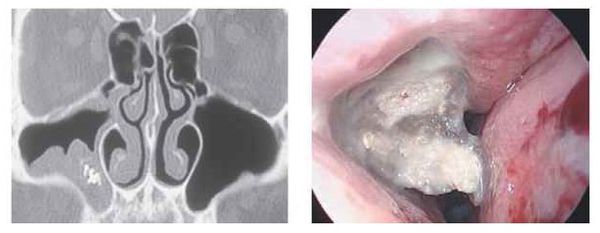

Инструментальная диагностика

Стандартные рентгенологические методы недостаточно информативны, поскольку они не могут дать объёмную послойную картину черепа, как КТ. На рентгенограммах утолщённая воспалённая слизистая оболочка пазухи имеет серый цвет, участки кальцификатов, которые образуют грибы мицетомы, — белый, а воздух — чёрный. Эти участки характерны только для мицетомы.

Мультиспиральная компьютерная томография остаётся эффективным и единственным способом диагностики мицетомы околоносовой пазухи. Использование трёхмерной реконструкции даёт представление об объёмном взаиморасположении костей, позволяет оценить состояние верхнечелюстной пазухи и зубочелюстной системы (целостность зубов, степень разрушения, цвет, положение в зубном ряду, подвижность, глубину зубодесневых каналов), а при наличии инородных тел точно показывает их форму, размер и местонахождение.

Мицетома в гайморовой пазухе на снимке КТ